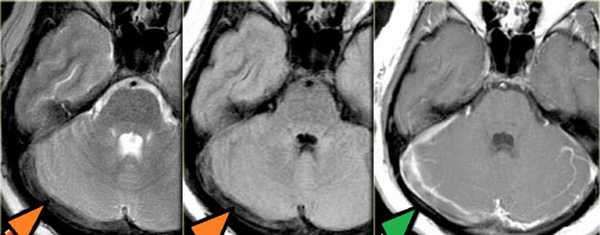

Тромбоз правого поперечного синуса - гипоинтенсивные участки по Т2 (внутриклеточный дезоксигемоглобин).

МР-венография: тромбоз правого поперечного синуса. Отмечается потеря МР-сигнала от правого поперечного синуса.

Тромбоз правого поперечного синуса. Отсутствие феномена «пустоты потока» от правого поперечного синуса на МРТ головного мозга. Отсутствие визуализации правого поперечного синуса на МР-венографии.